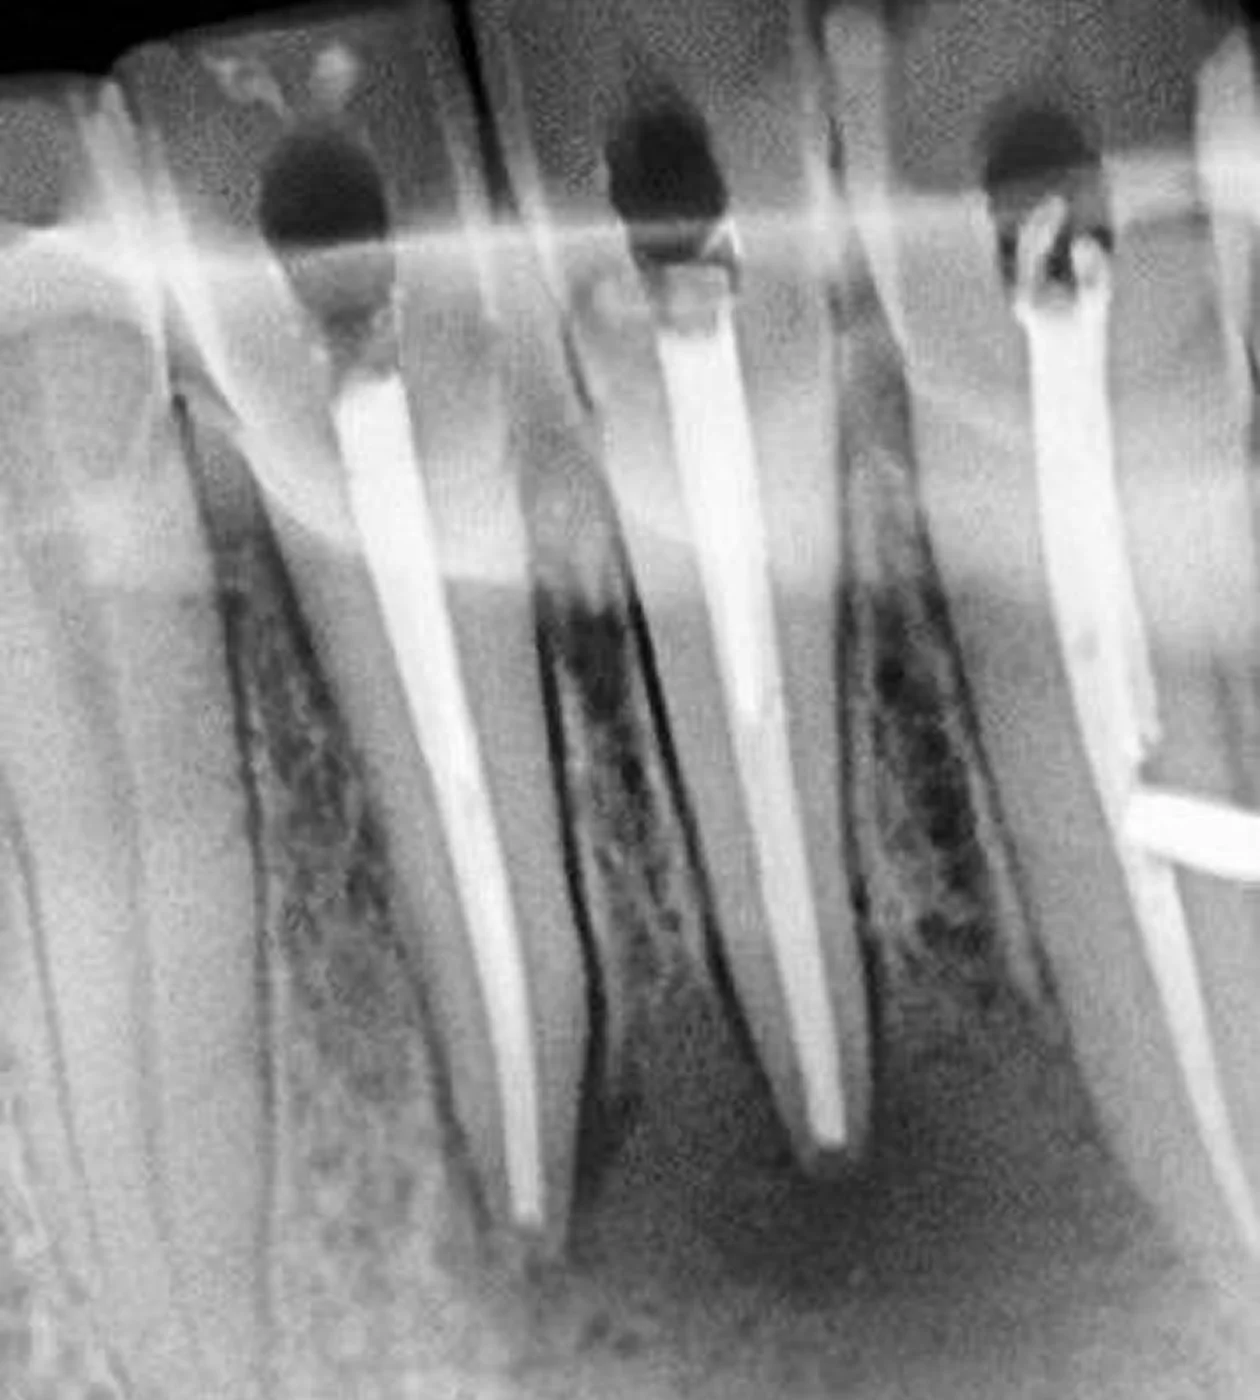

Ендодонтія (лікування кореневих каналів)

Лікування проводить Дарчия Марина Володимирівна — лікар мікро-ендодонтії з багаторічним досвідом та безперервним навчанням у кращих фахівців.

Основний напрямок: лікування найскладніших кореневих каналів та рятування раніше неправильно лікованих зубів.

В своїй роботі використовує сучасний та потужний мікроскоп та передові протоколи лікування.

09 Що таке мікроендодонтія?

У нашій клініці лікар-ендодонтист проводить первинне лікування та повторне лікування складних кореневих каналів із використанням сучасного дентального мікроскопа.

Завдяки оптичному збільшенню, професійному підходу та постійному вдосконаленню фахівця вдається проводити високоточне лікування навіть у складних випадках.